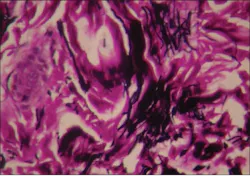

Collagen exists in many different forms, and each has a unique function within our bodies. For example, collagen type I forms the scaffolds for mineralized tissues and is the major component in all connective tissue. A good example would be the periodontal ligament (PDL) that is comprised of collagen type I (80%) and type III (20%), with lesser amounts of several other types of collagen.3 When there is disruption in collagen formation or when it is poorly synthesized, the bones, teeth, and various structures are weakened and the structural foundation is impaired.